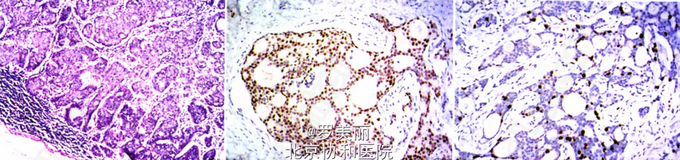

主诉:发现右乳腺肿块1周;现病史:患者男性,7l岁,因右乳腺肿块1周就诊。眼观:乳腺组织大小12 cm x 10 cm x 3 cm,乳头下可见一大小1.5 cm×1.0 cm灰白色肿块,界限不清。

3、查体:乳晕下可触及一2 cm×1 cm大小肿块,质硬,边界不清,欠光滑,无压痛,乳头无溢液,稍内陷,皮肤无破溃乳头。辅助检查:门诊彩超提示:右侧乳腺实质性包块,双侧乳腺增生,乳腺穿刺组织活检提示为乳腺癌。

4、诊断:乳腺癌;处理:行乳腺癌改良根治术,病理结果:(1)右侧乳腺浸润性筛状癌,侵犯乳头真皮组织;(2)右侧腋窝淋巴结4/21枚可见癌转移。

5、右侧乳腺浸润性筛状癌是一种罕见的乳腺癌,发病率约1%,其本例患者为男性,更是极为罕见,临床症状是无痛性包块,肿块内有微钙化灶。